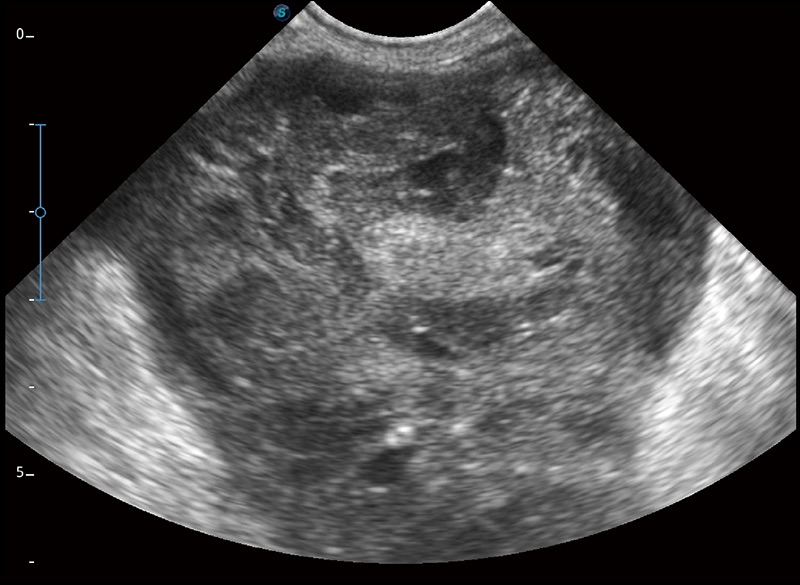

穿刺针增强

高清显示穿刺进针情况

连续波多普勒成像CW

为心脏功能评估提供更多诊断信息